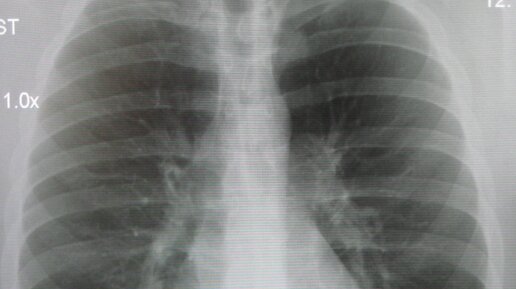

Как правильно проходить флюорографию? Советы специалистов

О том, как правильно проходить флюорографию и для чего она нужна рассказала главный специалист отдела мониторинга скрининговых программ Департамента профилактики неинфекционных заболеваний Национального центра общественного здравоохранения Гульжан Конуршина. «Флюорография грудной клетки – профилактический и диагностический метод рентгенологического обследования органов грудной полости и легких. Флюорография грудной клетки является скрининговым исследованием для выявления рака, туберкулеза и профессиональных болезней легких», - говорит специалист...